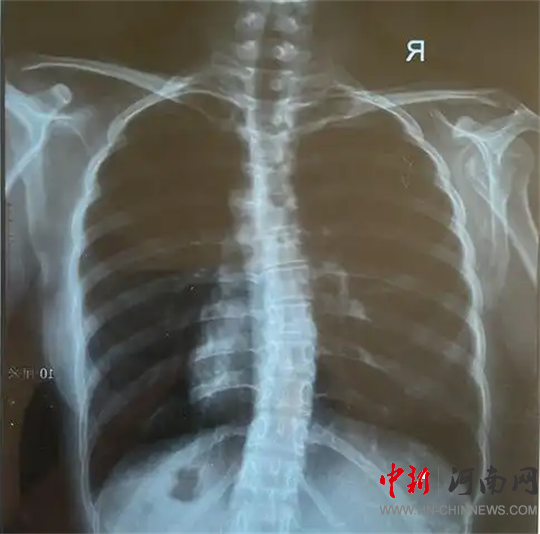

檢查結(jié)果為

脊柱側(cè)彎!

脊柱側(cè)彎,又稱脊柱側(cè)凸,是指脊柱偏離正中位置,身體向一側(cè)彎曲的骨骼畸形。

脊柱側(cè)彎絕大部分發(fā)生在青少年時(shí)期,是嚴(yán)重危及青少年群體身心健康的常見(jiàn)疾病,具有發(fā)病率高、起病隱匿等特點(diǎn),發(fā)病高峰集中在10-14歲。